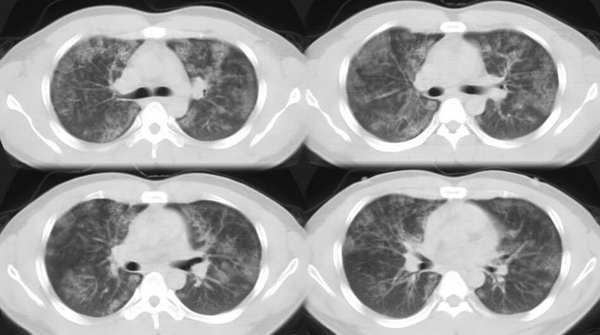

以下是引用ssl1_1在2006-3-2 22:37:00的发言:[br]肺泡蛋白沉积症(外围型)

以下是引用huangaiying1在2006-3-3 16:03:00的发言:[br]双肺弥漫分布的磨玻璃影及小结节影,以双上肺为著,纵隔内未见明显增大的淋巴结影,结合病史,考虑过敏性肺炎

以下是引用guandong在2006-3-4 20:57:00的发言:[br]两肺弥漫分布磨玻璃影,以中外带为主,可见于过敏性肺炎、肺泡蛋白沉着症、农民肺等,但不支持结核。